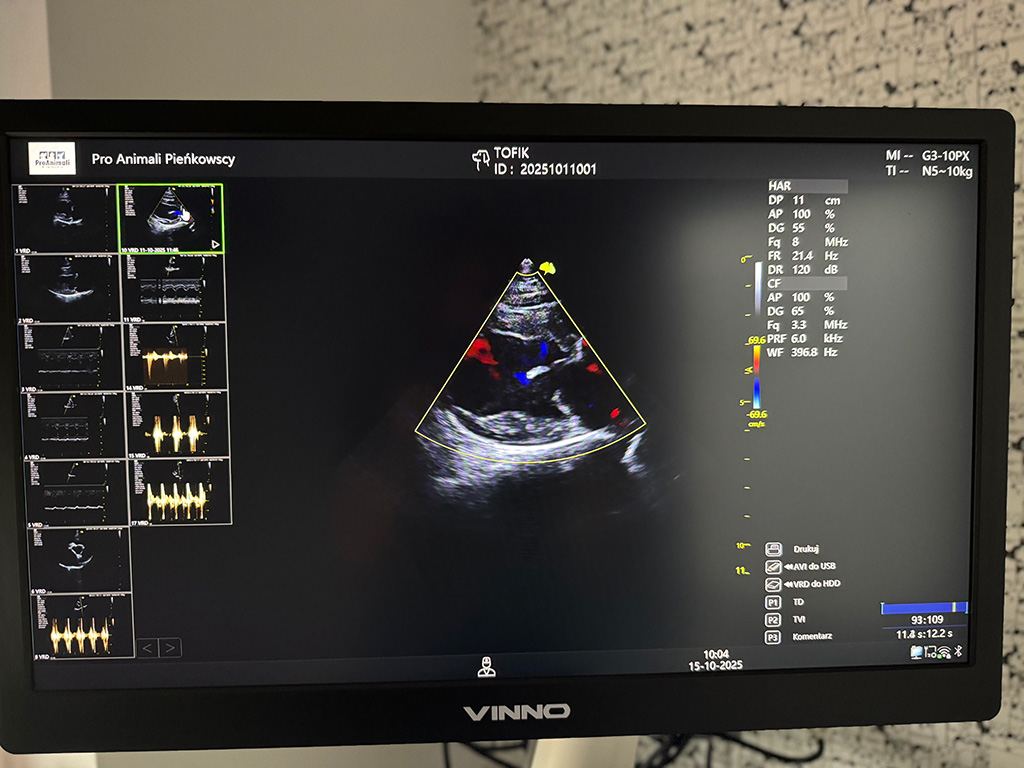

USG - Aparat USG klasy superpremium Vinno Norax R700:

• narządów jamy brzusznej

• układu moczowego

• układu płciowego

• narządów klatki piersiowej (płuc/serca)

• diagnostyka ciąży dopler kolorowy